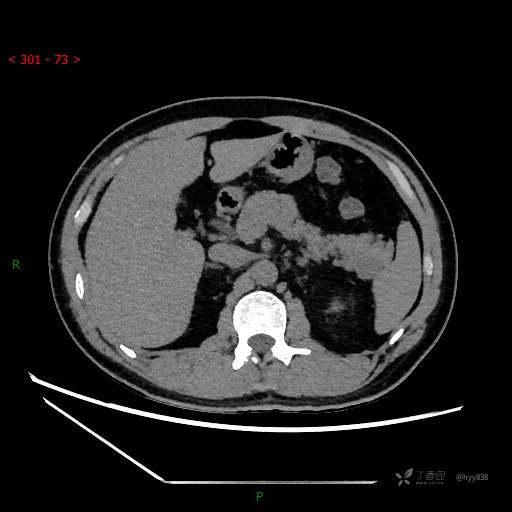

胰腺CT平扫

增强动脉期

增强静脉期

CT值

42hu 48hu 57hu